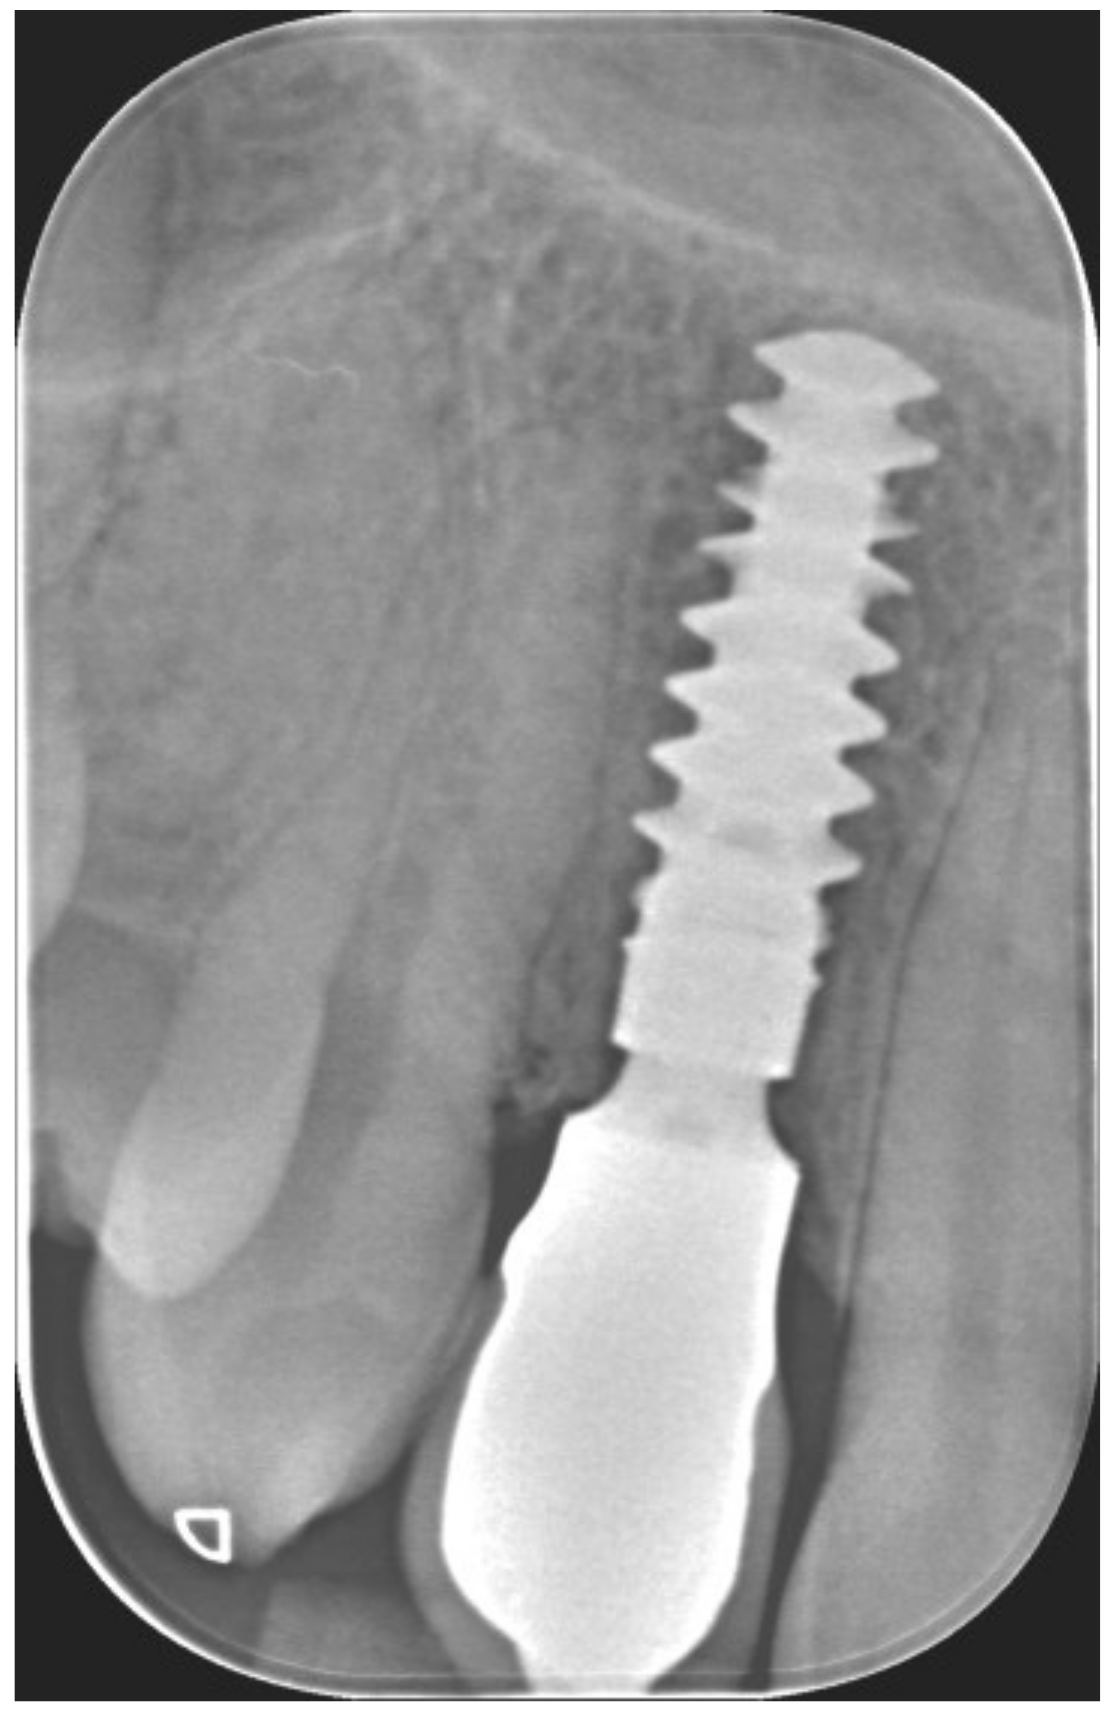

Figure 3.

Periapical X-ray showing deciduous canine.

Periapical X-ray at immediate temporization.

Periapical X-ray at 1 year of follow-up.